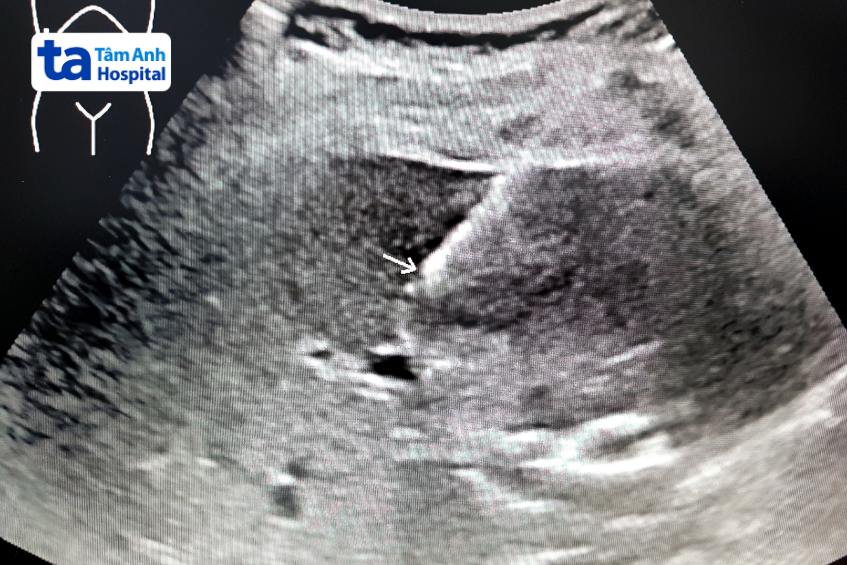

Sinh thiết gan dưới hướng dẫn siêu âm được xem là tiêu chuẩn vàng trong việc đánh giá một số tổn thương gan thường gặp. Quy trình thực hiện nhanh, độ chính xác cao và hiếm khi gây ra biến chứng nghiêm trọng.

Sinh thiết gan dưới hướng dẫn siêu âm là thủ thuật giúp chẩn đoán các tình trạng bất thường ở gan. Trong quá trình thực hiện, bác sĩ sẽ lấy một mẫu mô gan nhỏ và mang đi kiểm tra dưới kính hiển vi. Thông qua kết quả, bác sĩ có thể đánh giá được sức khỏe của gan, nguyên nhân gan bị tổn thương cũng mức độ nghiêm trọng mà người bệnh gan đang gặp phải. Phương pháp sinh thiết gan phổ biến nhất là sinh thiết qua da. Thời gian nằm viện 2 ngày, ngày 1 làm thủ tục xét nghiệm đông máu và thực hiện thủ thuật, bệnh nhân có thể xuất viện vào ngày 2 nếu bệnh ổn.

Bác sĩ sẽ thực hiện đánh giá trước khi làm thủ thuật, sau đó tiến hành truyền thuốc kháng sinh dự phòng, an thần, thuốc giảm đau trước khi làm thủ thuật. Lúc này, do tác dụng của thuốc, người bệnh có thể cảm thấy buồn ngủ. Các bước tiến hành tiếp theo như sau: